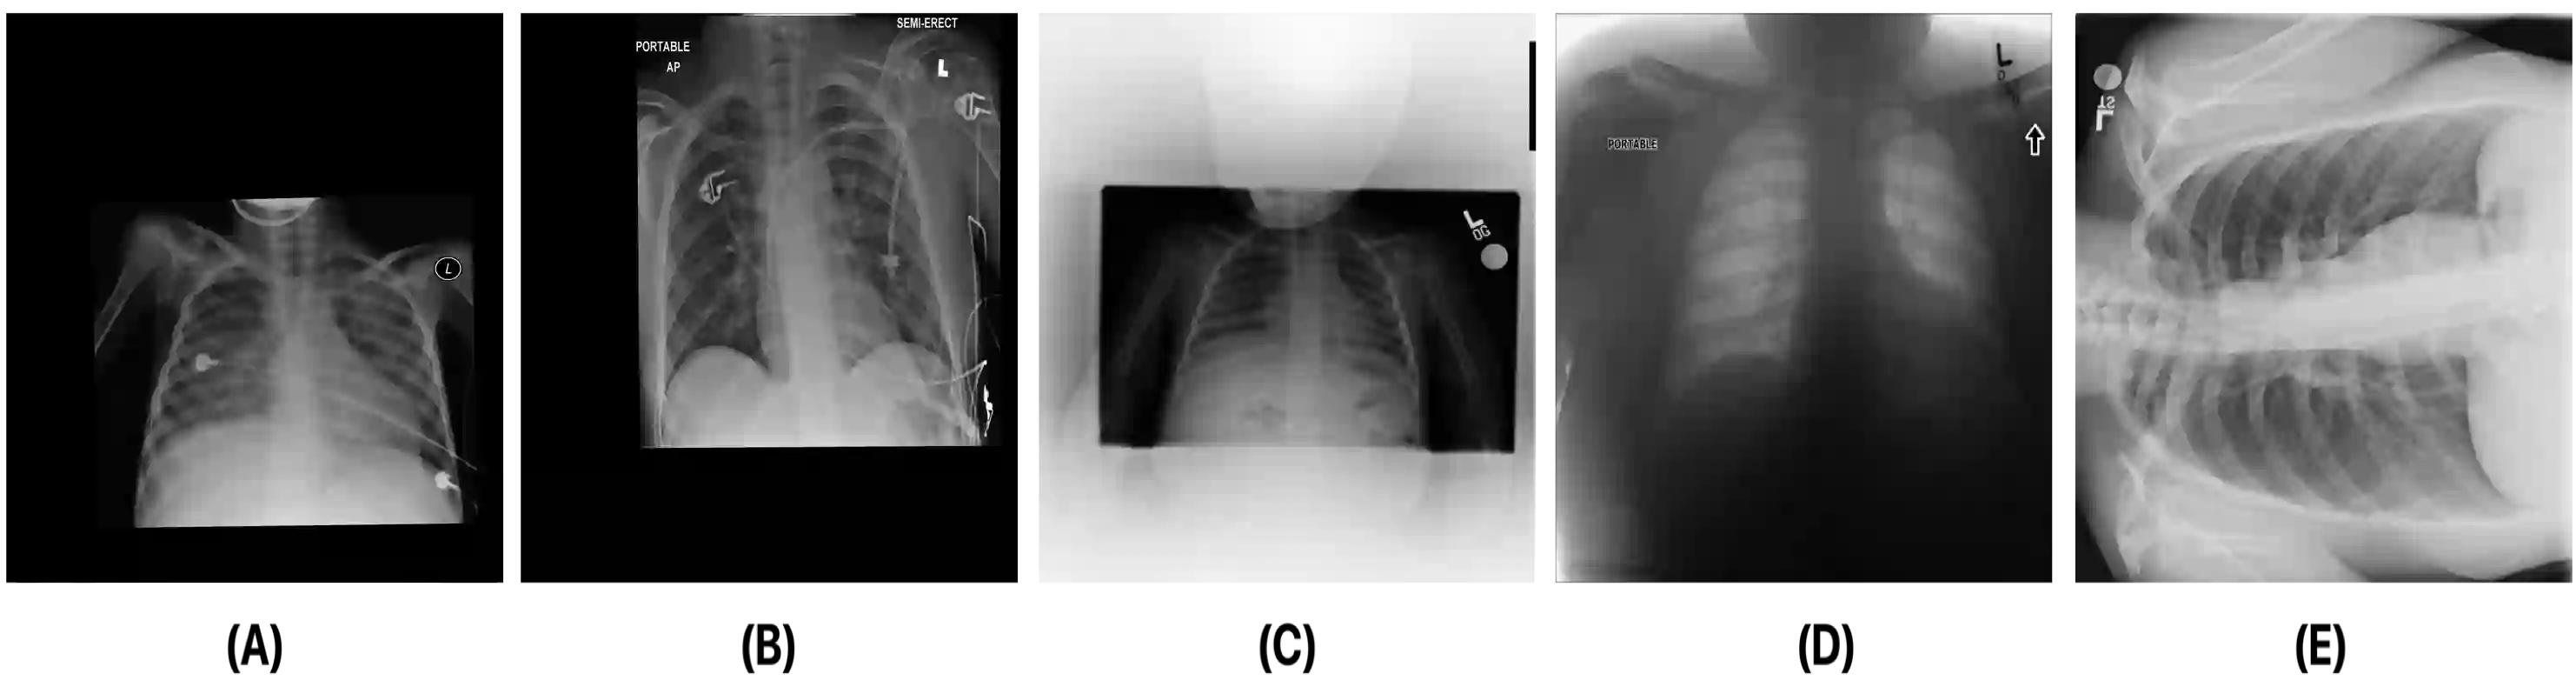

Medical image analysis continues to hold interesting challenges given the subtle characteristics of certain diseases and the significant overlap in appearance between diseases. In this work, we explore the concept of self-attention for tackling such subtleties in and between diseases. To this end, we introduce MEDUSA, a multi-scale encoder-decoder self-attention mechanism tailored for medical image analysis. While self-attention deep convolutional neural network architectures in existing literature center around the notion of multiple isolated lightweight attention mechanisms with limited individual capacities being incorporated at different points in the network architecture, MEDUSA takes a significant departure from this notion by possessing a single, unified self-attention mechanism with significantly higher capacity with multiple attention heads feeding into different scales in the network architecture. To the best of the authors' knowledge, this is the first "single body, multi-scale heads" realization of self-attention and enables explicit global context amongst selective attention at different levels of representational abstractions while still enabling differing local attention context at individual levels of abstractions. With MEDUSA, we obtain state-of-the-art performance on multiple challenging medical image analysis benchmarks including COVIDx, RSNA RICORD, and RSNA Pneumonia Challenge when compared to previous work. Our MEDUSA model is publicly available.